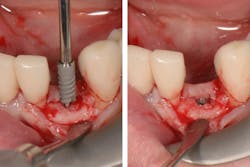

Placement of narrow implants. In a full-arch restoration in the presence of alveolae and thin ridges, narrow implants allow the placement of more biomaterial in the alveolae for ridge preservation. Bone grafting will be avoided in the presence of the ridges.